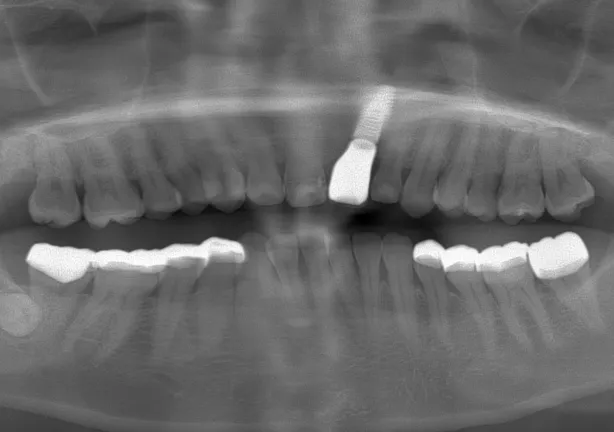

case1

Before

治療内容 | 口腔内診査〜カウンセリング 歯周初期治療 仮の義歯にて噛む位置の再設定 インプラント埋入 仮歯にてインプラントを含めた噛む位置の決定 最終的な被せ物(ジルコニア)の型取り〜装着 |

---|---|

治療期間 | 3年 |

治療回数 | 100回 |

リスク | 手術、並びに治療における疼痛 今後のメンテナンスが必須となる |

費用(税込) | 約¥11,000,000 |